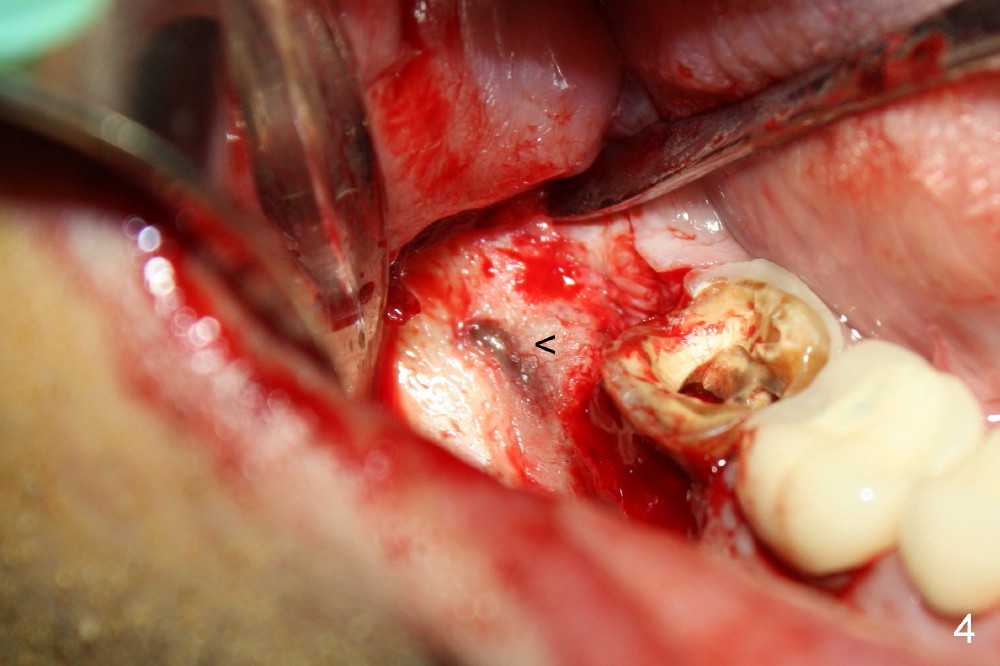

indicated by Fig.3 arrowheads. The bone is resorbed on the top of the cyst

(Fig.4<). A bony window is made (Fig.5*) to expose the impacted tooth of

#32 (Fig.6). The latter is sectioned for easy removal (Fig.7 arrowhead);

there is yellowish exudate from the cyst (*). Nonsalvageability of #31 is

confirmed (Fig.8). Extraction of #31 shows the septum (Fig.9).